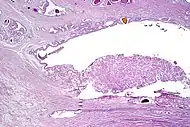

| Intraductal adenocarcinoma | 2.8%[10] | ![]() H&E and CK5/6 |

Intraductal carcinoma of the prostate with an infiltrative growth pattern may be morphologically difficult to distinguish from invasive cancer. One focus shows comedonecrosis (arrow), morphologically suggesting Gleason pattern 5 invasive carcinoma (a haematoxylin and eosin, b CK5/6)[19]

Intraductal carcinoma of the prostate with very patchy basal cells identified by immunohistochemistry. At least some of the glands lacking basal cell immunoreactivity represent intraductal rather than invasive carcinoma (a haematoxylin and eosin, b CK 5/6)[19]